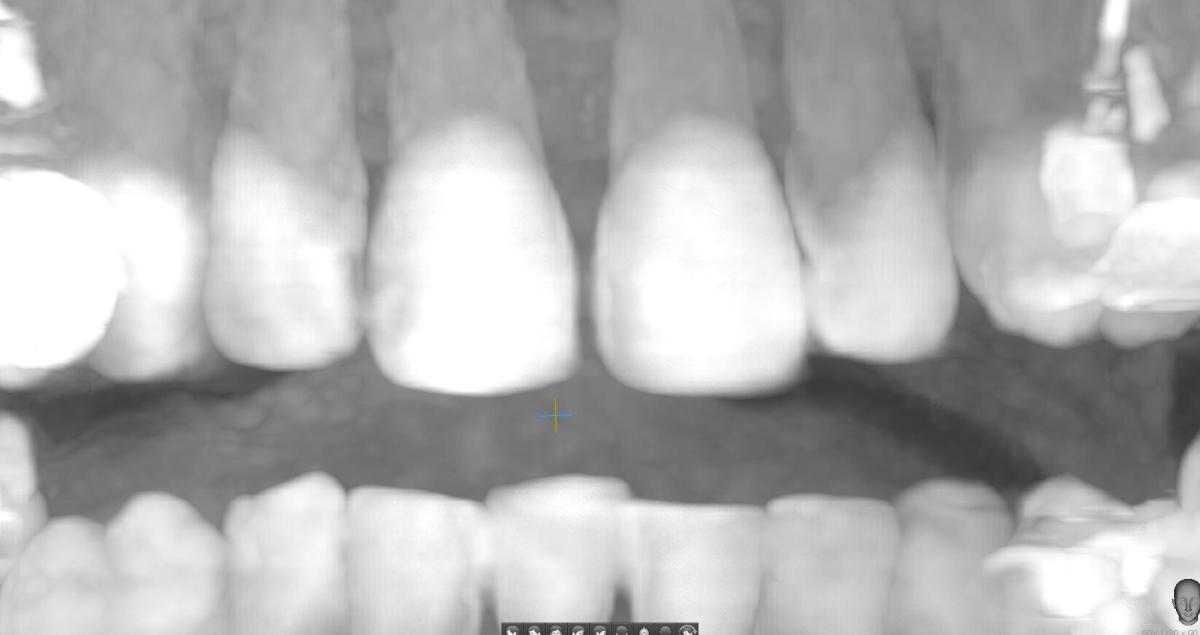

Здравствуйте, подскажите, светлый участок, может ли быть глубоким кариесом?

На эмали есть небольшое пятнышко после лечения Icon месяца 2 назад (пятно посветлело, но полностью не ушло).

Сейчас зуб начал болеть, на холодное/горячее не реагирует, просто болит.

Вчера сделала КТ.

Юрий Жигурт, Подскажите, пожалуйста, есть ли кариес на 11 зубе (сторона контактная с 12 зубом)? Или его признаки. Если да, то насколько глубоко? Если возможно покажите, пожалуйста, стрелочкой где это наблюдается. Спасибо!

anastasiiia, есть основания предполагать:

Я была у нескольких врачей, один сказал - трогать не стоит, возможно не будет развиваться или крайне медленно будет развиваться, второй сказал, что вообще ничего нет в дентине. Но у меня сомнения(